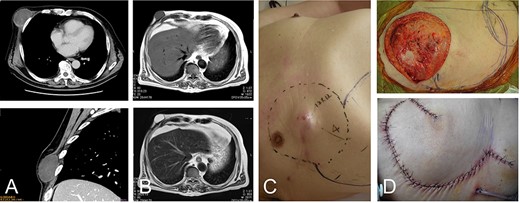

A 42-year-old man presented with a history of a mass on his right chest wall that gradually increased in size over 2–3 years. On physical examination, a protuberant hard, immobile elastic mass that appeared attached to the fascia was palpable on the anterior chest wall. Magnetic resonance imaging (MRI) revealed an 8 × 12-cm subcutaneous tumor. The tumor showed homogenous low-signal intensity on the T1-weighted image and high-signal intensity on the T2-weighted image (Fig. 1A and B). The tumor was attached to the fascia of the pectoralis major muscle.

42-year-old male with dermatofibrosarcoma protuberans in the chest wall. Magnetic resonance imaging shows the subcutaneous tumor with low-signal intensity on the T1-weighted image (A) and slightly high-signal intensity on the T2-weighted image (B-upper) and high-signal intensity on a T2-weighted fat-suppressed image (B-lower); photograph of ulcerated subcutaneous lesion with subcutaneous extension; after resection of the tumor with the surrounding tissue (C), the defect was reconstructed with a thoracoabdominal flap (D).

Histological examination of a needle biopsy specimen revealed a dermatofibrosarcoma protuberans. The tumor was resected along with the surrounding skin, subcutaneous tissue, and the underlying pectoralis major muscle, leaving a defect of 16 cm in the maximum diameter (Fig. 1C). The defect was reconstructed with a medially-based thoracoabdominal flap (Fig. 1D).